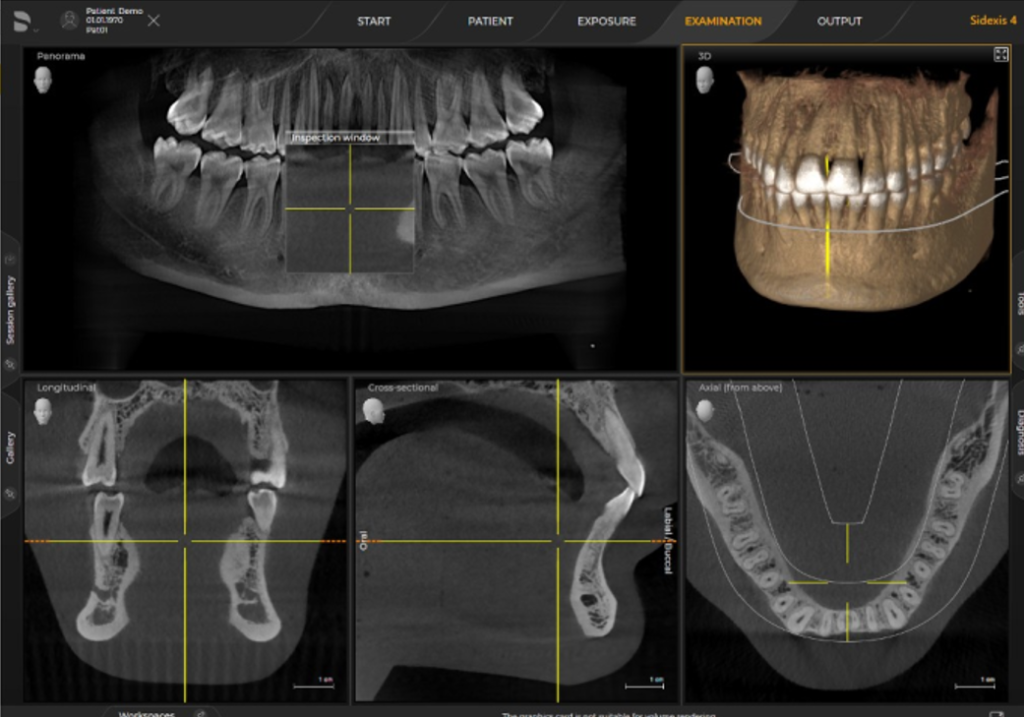

ORTHOPHOS SL 3D. Довершена рентгенівська система для будь якої практики.

ORTHOPHOS S 3D це прилад з всеохоплюючими можливостями. Починаючи з надчітких панорамних 2D знімків завдяки сучасному DCS сенсору і аж до максимальної гнучкості у виборі 3D обєму зйомки (11Х10, 8Х8, 5Х5). У коплексі з програмним забезпеченням SIDEXIS 4 відкриє нові можливості для Вашої практики.

Три розміри об'єму зйомки на вибір

Точність для вірної діагностики та ефективне використання часу

Поле огляду 8 см х 8 см (VOL1) дозволяє відобразити всю щелепу пацієнта на одному знімку, що спрощує діагностику та планування лікування. При ендодонтичному лікуванні достатньо меншого обєму 5смХ5,5см (VOL2). Таким чином ми не тільки зменшуємо дозу опромінення а й скорочуємо час на постановку діагнозу. В режимі HD (висока роздільна здатність, 500 знімків зо один оборот ) при VOL2 з розміром вокселя 100 мкм Ви отримаєте надчіткі знімки для ендодонтичного лікування. Обєм 11 см Х 10 см надасть Вам максимум потрібної інформації.